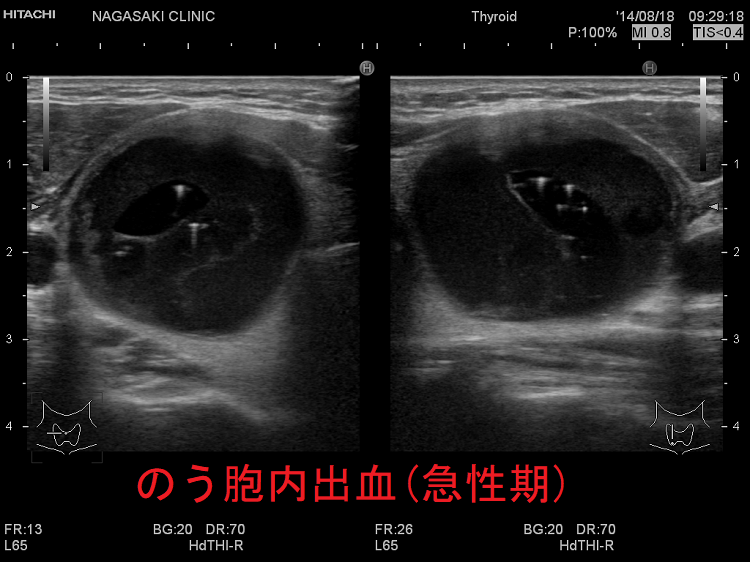

亜急性甲状腺炎

亜急性甲状腺炎は、甲状腺に痛みや不快感を引き起こす、まれなタイプの甲状腺炎です。この疾患を持つ人は甲状腺機能亢進症の症状も示し、その後甲状腺機能低下症の症状を発症します。亜急性甲状腺炎は一時的なことが多いですが、治療せずに放置すると永続的な合併症を引き起こす可能性があります。